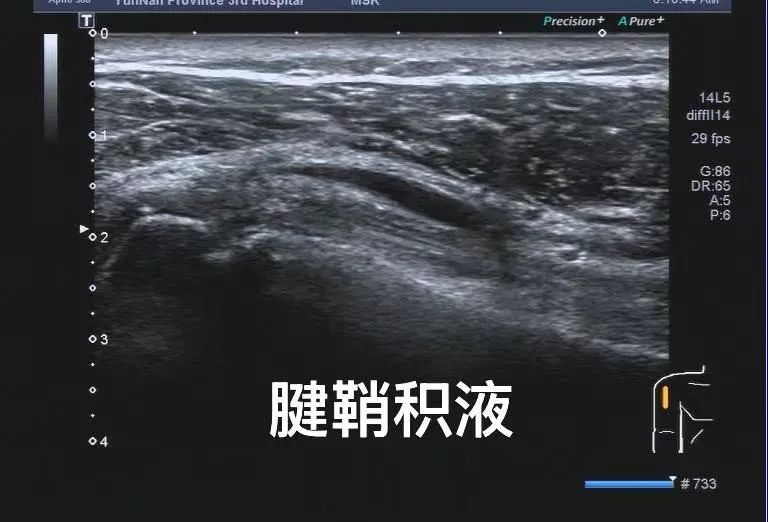

肌骨超声是利用高频超声波探头(通常频率在7-18 MHz),对人体肌肉、肌腱、韧带、神经、关节等软组织进行实时动态成像。与传统X光、CT只能显示骨骼结构不同,肌骨超声能清晰捕捉到肌肉撕裂、肌腱炎症、韧带损伤、关节积液等细微病变,堪称“无创显微镜”。

3. 高分辨率,细节清晰

高频探头能分辨0.1毫米的细微结构,比如肌腱的微小撕裂、神经的卡压或肿胀,甚至能发现早期的痛风结晶沉积。